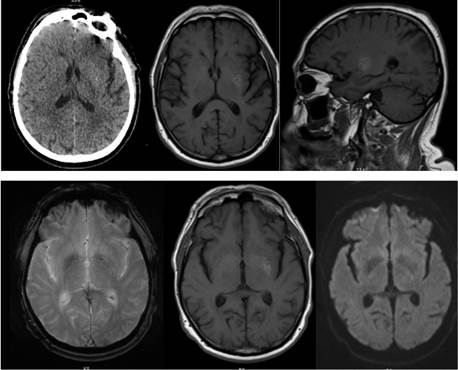

Se realizó una TC de cráneo sin elementos de isquemia aguda ni sangrados, mientras que la RM de cráneo evidenció una hiperintensidad a nivel del putamen izquierdo en la secuencia T1. Figura 1.

La TC de cráneo evidenció una leve hiperdensidad gangliobasal izquierda, que se correspondió con una hiperintensidad en el putamen izquierdo en T1 en la RM de cráneo. Las secuencias de ecogradiente y difusión en la RM no mostraron alteraciones, apoyando el planteo de estriatopatía diabética. Figura 2.

Figura 2: Tomografía computada (TC) y Resonancia magnética (RM) de cráneo. En la fila superior se muestra un corte axial de TC de cráneo y cortes axial y sagital en T1 (RM). En la fila inferior se muestran cortes axiales de secuencia ecogradiente, T1 y difusión (en orden de izquierda a derecha).

La neuroimagen en la estriatopatía diabética, característicamente muestra aumento de señal en el núcleo estriado, tanto en la TC como en la secuencia T1 en la RM, con la correspondiente hipointensidad en secuencias T2.1-6 Dicho cambio de señal generalmente es contralateral con respecto a la corea, pudiendo presentarse en algunos pacientes de forma bilateral.6)

Nuestros pacientes se presentaron ambos con hiperintensidad de señal en T1 en el putamen izquierdo, concordando con dicha predilección.